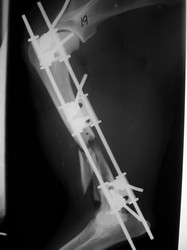

Fijación Externa

PRÁCTICAS CURSO DE FIJACIÓN EXTERNA PERFECCIONAMIENTO.

Húmero.